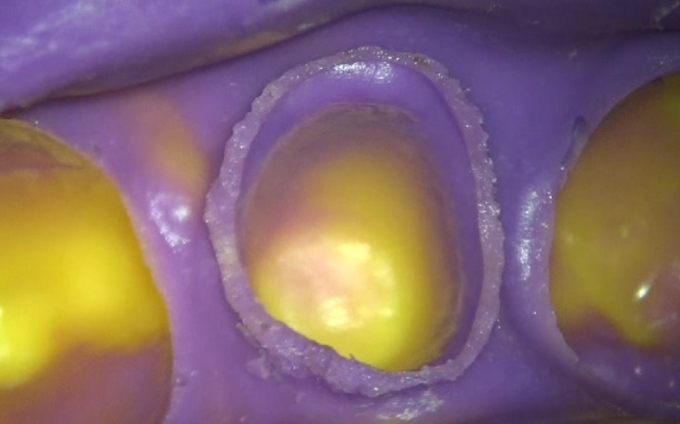

南館歯科クリニックでは、最終補綴物の精度に大きく影響を与える支台歯形成と印象採得をマイクロスコープ下で行います。この分野は、残念ながら歯科医師の技術に左右されます。

最終補綴物と歯の境目となるマージンといわれる部分を、マイクロスコープを使って正確に形成し、専用のシリコン材で明瞭に記録を採ることにより、極めて適合の良い被せ物や詰め物を作製することが可能となります。